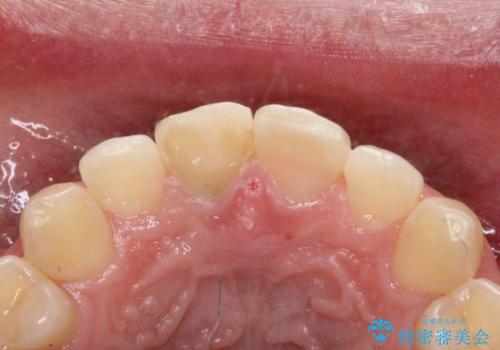

治療手順としましては、マイクロスコープ(歯科用顕微鏡)を使用し、元々入っていた詰め物のCR(プラスチック)を除去します。その後、歯の中に薬剤を入れ、蓋をします。2週間後に来院して頂き、白くなっているかを確認します。ご本人がご満足頂く白さになるまで、これを3~4回繰り返します。今回は1回で患者様がご満足されたので治療を終了しています。

精度を高めるために当院はマイクロスコープを使用しています。